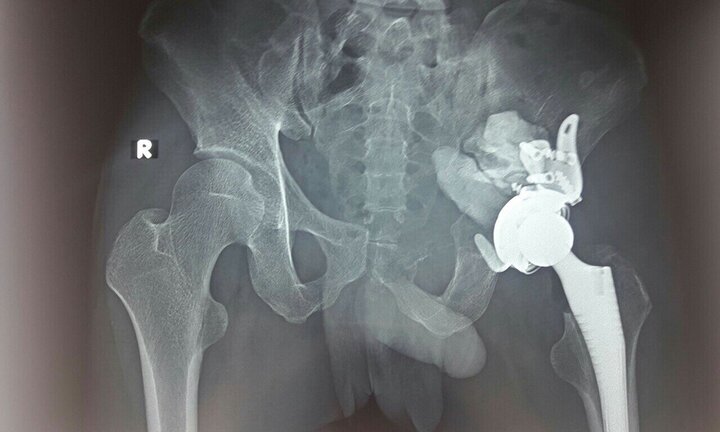

Khối u ở vùng cổ cối xương chậu khiến nam bệnh nhân bị đau khớp háng trái, tình trạng bệnh nặng hơn qua nhiều ngày khiến anh không chủ động đi lại được mà phải chống nạng.